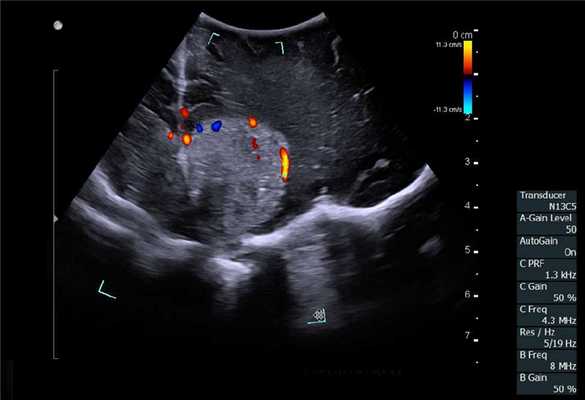

Нейрохирургия

Основная цель хирургического лечения злокачественных опухолей головного мозга - радикальная резекция опухоли при сохранении окружающей функциональной ткани мозга, что напрямую связано с увеличением продолжительности и улучшением качества жизни пациента [12]. Рамочные и безрамочные стереотаксические предоперационные нейронавигационные системы, обычно используются, чтобы помочь хирургам спланировать место краниотомии и идентифицировать критические нервные структуры. К сожалению, эти системы имеют проблемы, связанные с потерей точности в результате искажения, сдвига и деформации после краниотомии и удаления ткани опухоли [13]. В последнее время разработаны новые методы, включая интраоперационную диагностическую визуализацию (Intra-Operative Magnetic resonans) дороги и доступны не во всех нейрохирургический центр. Поэтому большое внимание уделяется возможностям интраоперационного использования УЗИ.

ИОУЗИ помогает локализовать опухоль, определить ее границы, а также провести осмотр зоны после удаления на предмет наличия остаточной опухолевой ткани и оценки радикальности выполненного вмешательства [14,15]. Его основными ограничениями являются пространственное разрешение, ширина и ориентация поля зрения (разные от стандартных ортогональных плоскостей КТ и МРТ) и качества сканирования, которые зависят от оператора.

Отечественные и зарубежные авторы доказали высокий уровень корреляции между данными, полученными при интраоперационном УЗИ и послеоперационной МРТ с контрастным усилением при обнаружении остаточной опухолевой ткани [16,17]. При этом применение режимов допплерографии, а также контрастного усиления значимо повышают информативность исследования. Цветовое допплеровское картирование при сосудистых аномалия позволяет не только локализовать аневризму, но и вместе со спектральной допплерографией провести оценку гемодинамических показателей, например, после клипирования аневризмы.